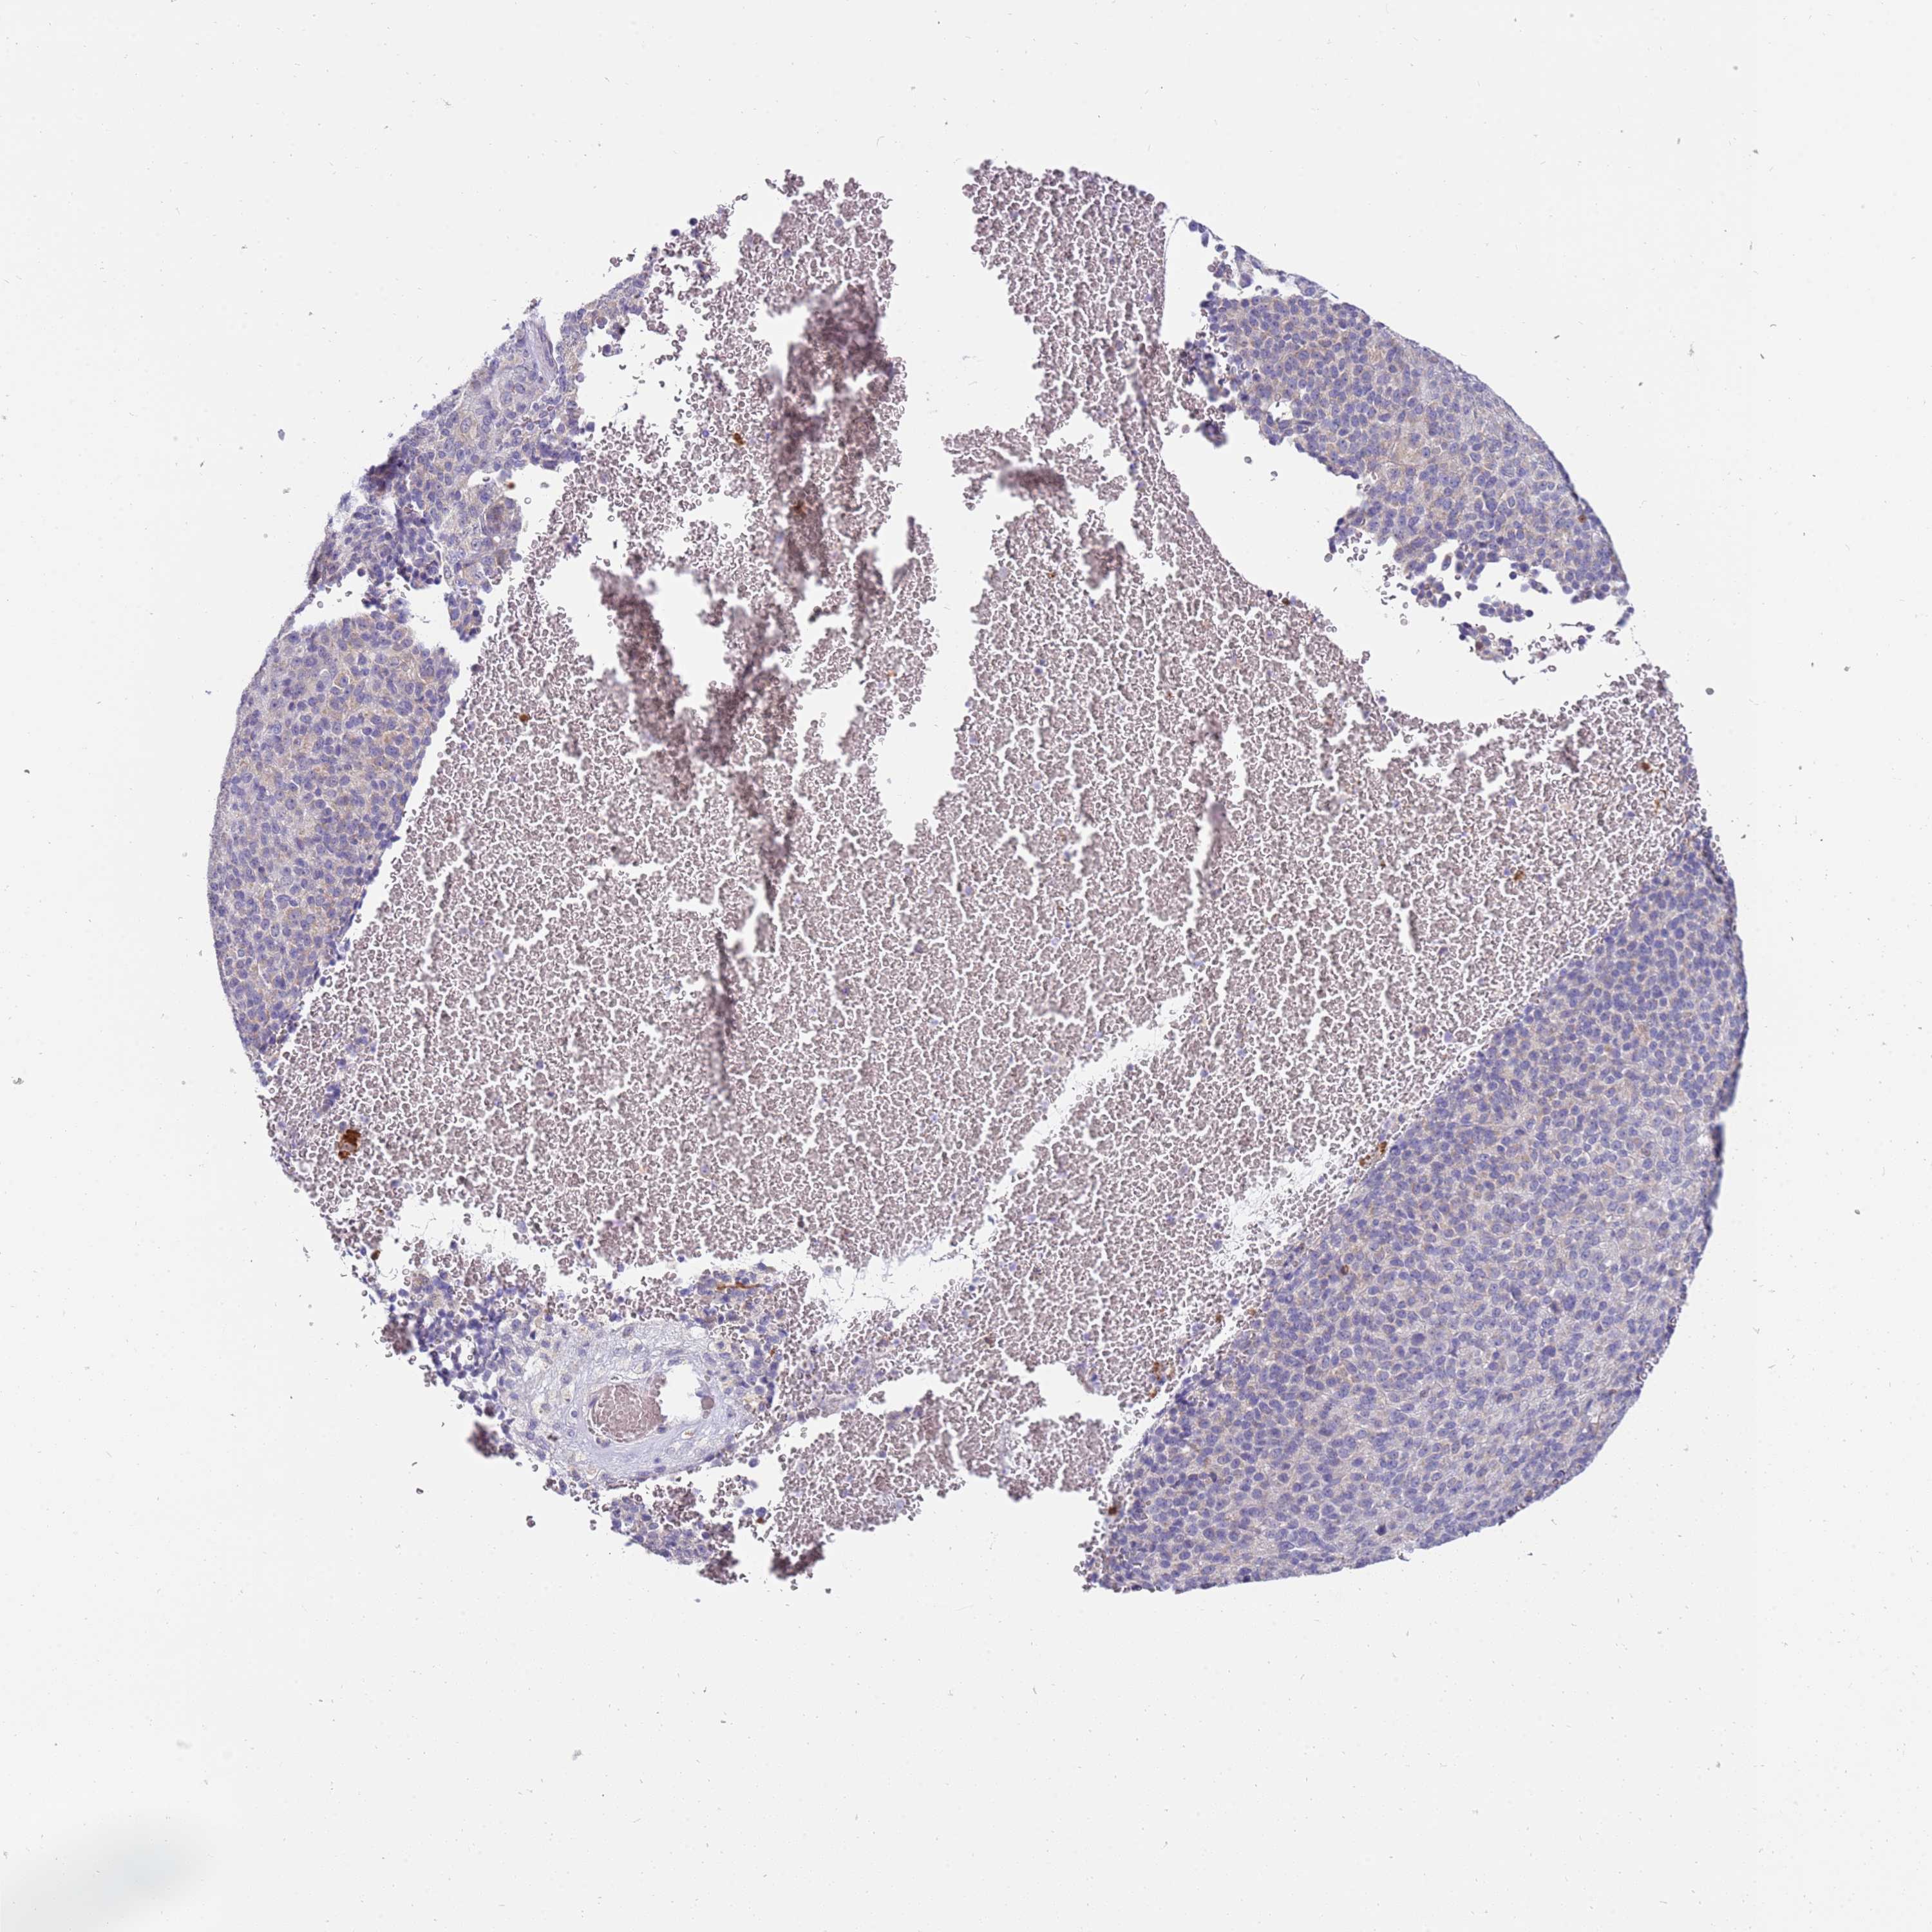

MELANOMA - Protein expressioni

A mouse-over function shows sample information and annotation data. Click on an image to view it in a full screen mode. Samples can be filtered based on level of antibody staining by selecting one or several of the following categories: high, medium, low and not detected. The assay and annotation is described here.

Note that samples used for immunohistochemistry by the Human Protein Atlas do not correspond to samples in the TCGA dataset.

Antibody stainingi

Antibody staining in the annotated cell types in the current human tissue is reported as not detected, low, medium, or high, based on conventional immunohistochemistry profiling in selected tissues. This score is based on the combination of the staining intensity and fraction of stained cells.

Each image is clickable and will lead to virtual microscopy that enables deeper exploration of all samples and also displays staining intensity scores, fraction scores and subcellular localization as well as patient and tissue information for each sample.

Antibody HPA047147

Staining

High

Medium

Low

Not detected

Intensity

Strong

Moderate

Weak

Negative

Quantity

>75%

75%-25%

<25%

None

Location

Nuclear

Cytoplasmic/membranous

Cytoplasmic/membranous,nuclear

Malignant melanoma, NOS

Malignant melanoma, Metastatic site